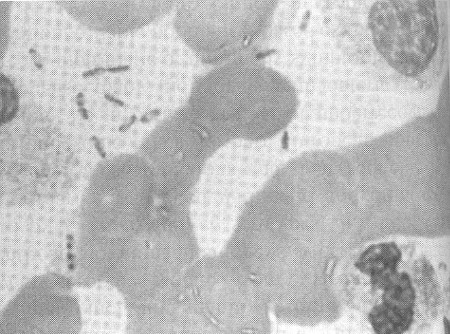

Panel B. Photo of the patient's hand

The patient had Y. pestis bacteremia with disseminated intravascular coagulation resulting in acral gangrene (left). Y. pestis is a Gram-negative bipolar coccobacillus shown here in a buffy coat examination of the patient's peripheral blood (right).